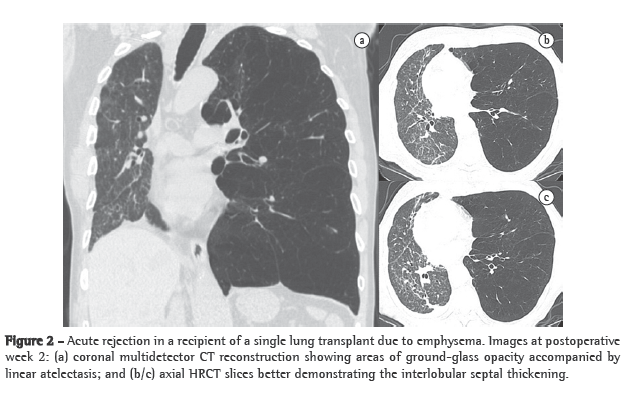

Acute rejection after transplantation is a common occurrence. Nearly 95% of patients present at least two episodes within the first month after surgery. Histologically, acute rejection is characterized by predominantly lymphocytic perivascular infiltrate, with or without bronchiolar involvement.(8) Symptoms are generally nonspecific, including low-grade fever, breathlessness and fatigue. Most patients experience at least one episode of acute rejection within the first 3 weeks and remain at high risk for this complication for the first 100 days after transplantation.(5) Chest X-ray findings are normal in up to 50% of cases.(6) The most common findings are perihilar and lower-lobe opacities, as well as interlobular septal thickening and pleural effusion (Figure 2).(9) The HRCT features are relatively nonspecific and include ground-glass opacities (often with basal distribution), peribronchial cuffing, septal thickening (interlobular and intralobular) and new or more extensive pleural effusion.(10) This complication can be almost completely excluded if there are no ground-glass opacities.(9) Acute rejection is treated with intravenous corticosteroids and typically responds quite well after 24 h of this treatment. A dramatic reduction in abnormal radiological features after 48 h of intravenous administration of methylprednisolone is indicative of a diagnosis of acute rejection.(9,10)